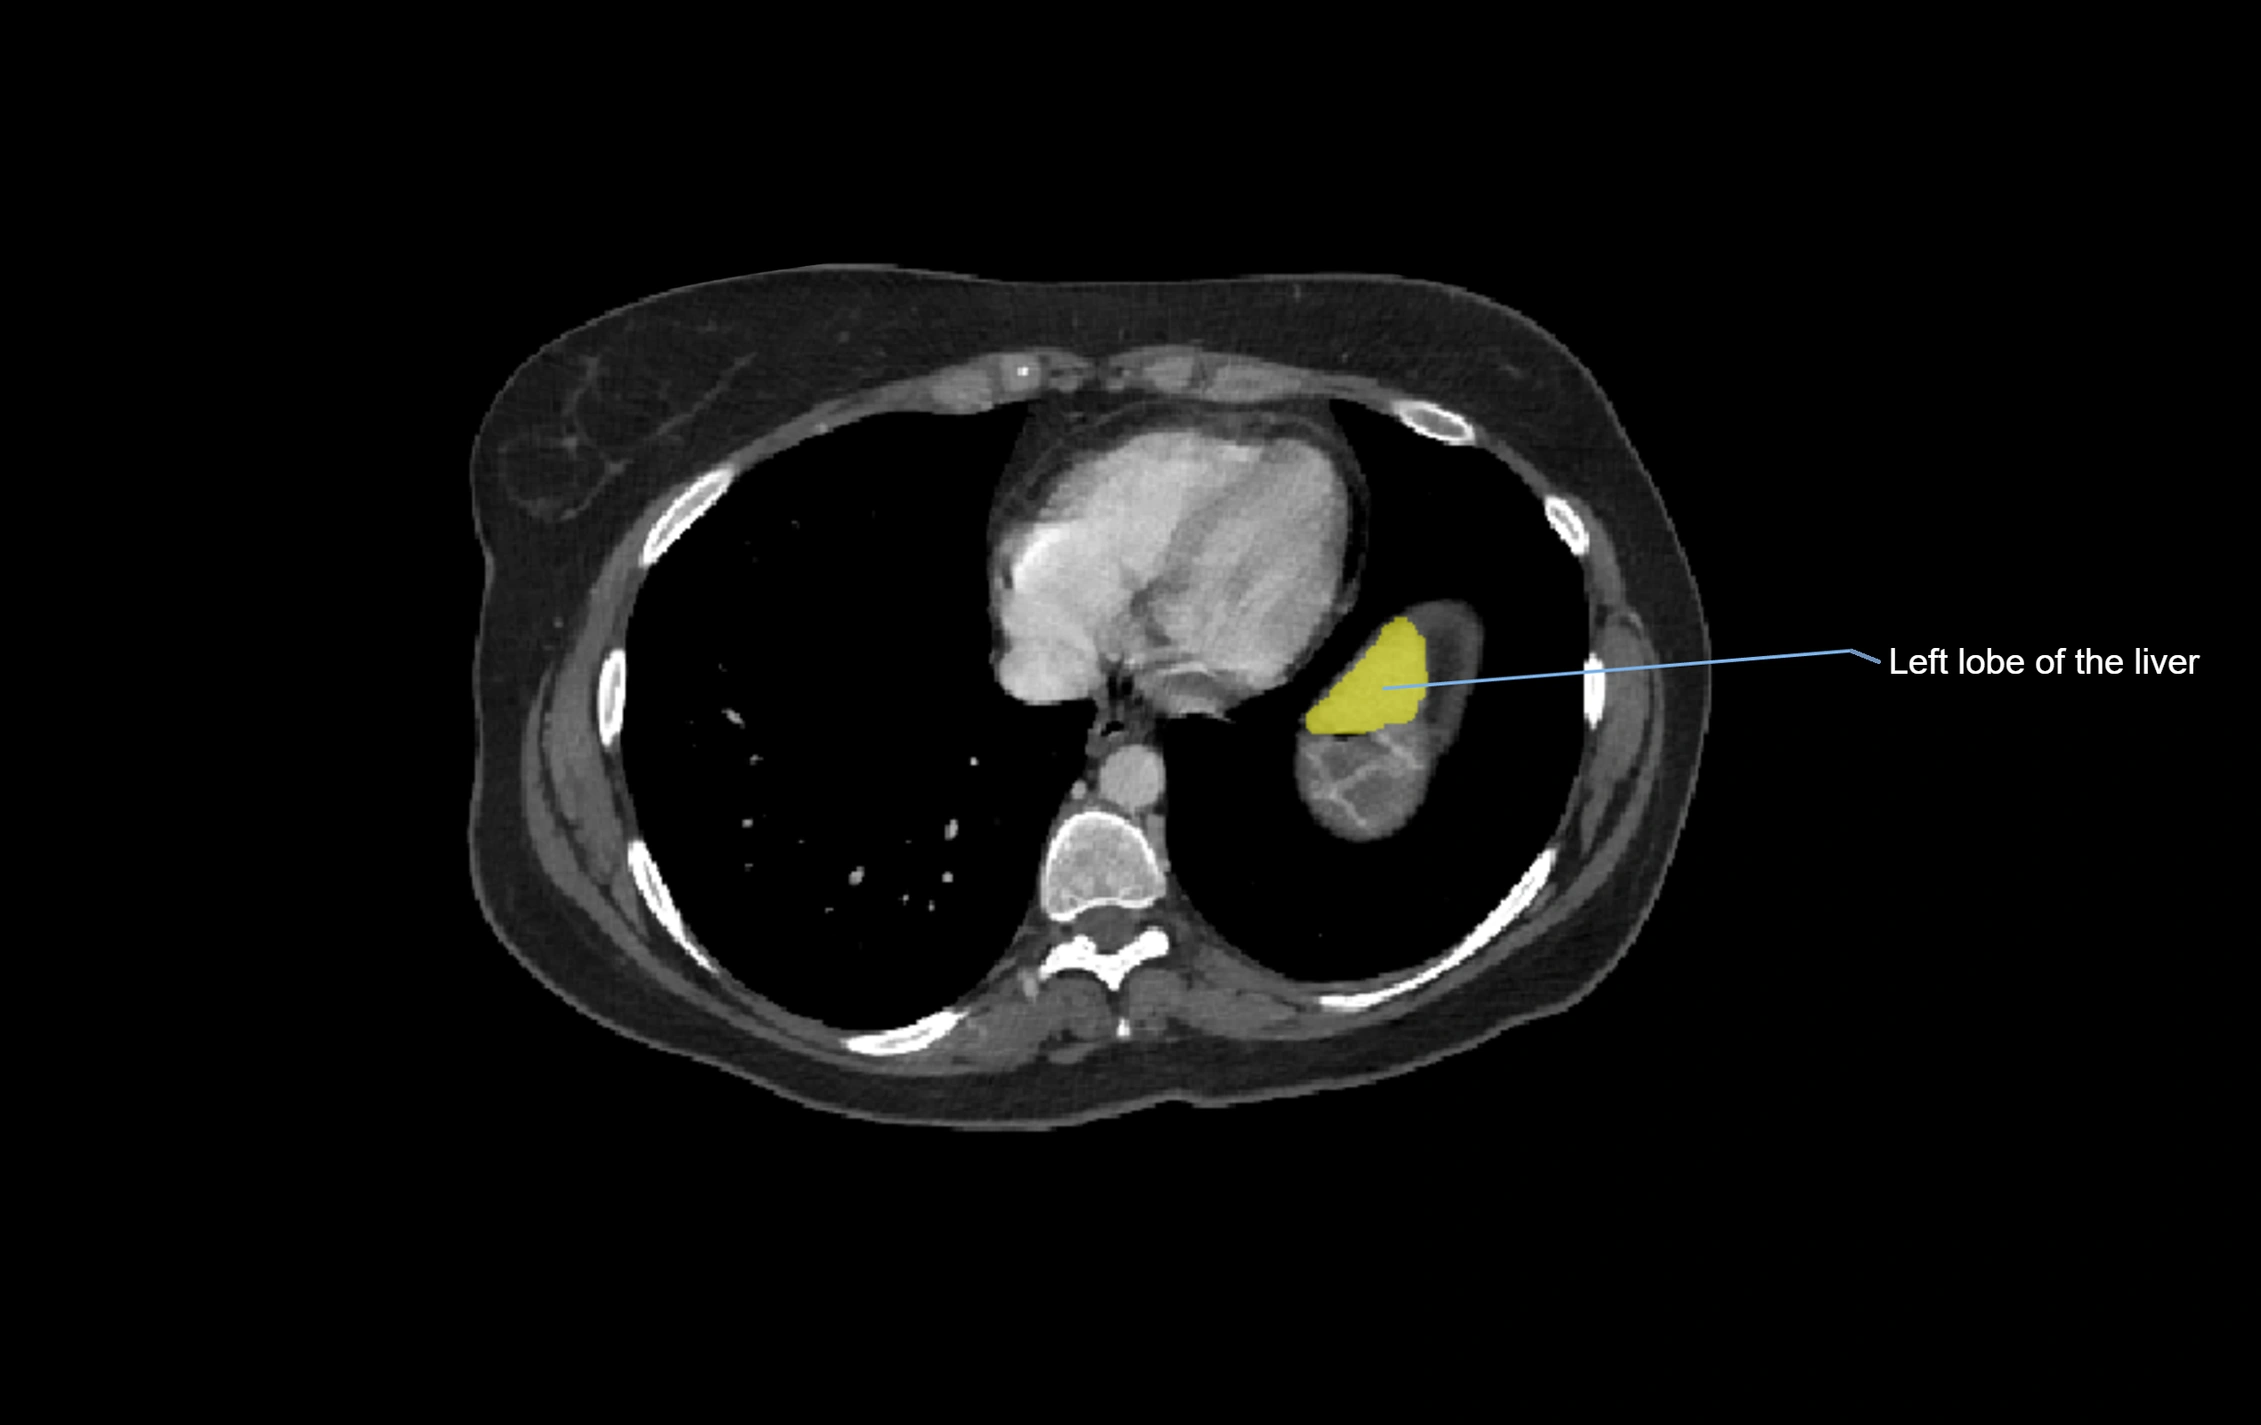

MRI image

image

MRI Appearance

T1-weighted images:

• Parenchyma shows intermediate signal intensity, similar to rest of liver

• Lesions (tumors, fat, fibrosis) show altered signal compared to background liver

T2-weighted images:

• Normal parenchyma shows intermediate to slightly hyperintense signal

• Pathologies (cysts, hemangiomas, tumors) demonstrate variable high signal